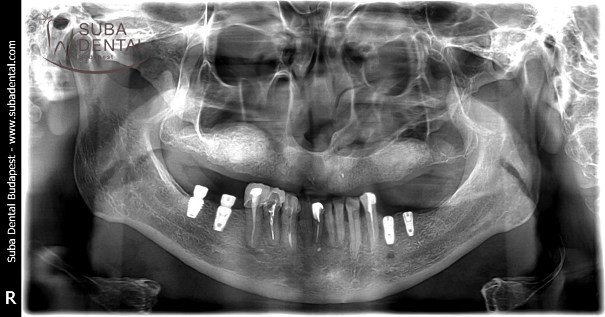

Panoramic radiograph following the mounting of 8 upper implants and the healing abutments